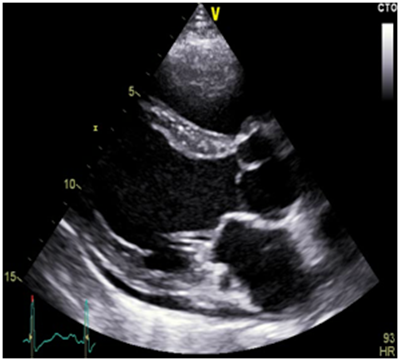

33 years old male patient, smoker, with a history of treated asthma , left posttraumatic pneumothorax with repeted pleurodesis, solved by surgery is admitted for dyspnea at rest, dry cough accentuated in clinostatism and cyanosis, symptoms that worsened two months before admission, onset two years ago. The clinical examination revealed a left latero-thoracic postsurgical scar, mixt cyanosis, rest dyspnea, dry cought, normal pulmonary auscultation, SpO2=97%, anterior chest pain, turgid jugular veins, tachycardia, BP=130/70mmHg, left parasternal continuous murmur of high intensity, accentuated by Valsalva maneuver, loud S 2 palpable in pulmonary area, systolic tricuspid murmur, no edemas, hepatomegaly and hepato-jugular reflux. Electrocardiogram (Figure 1) showed sinusal tachycardia, 120bpm, right bundle branch block, right axis deviation. The blood samples revealed myocardial and hepatic cytolyse, increased creatinine. On chest X-ray as showed in Figure 2 we found cardiomegalia, straight left middle cardiac arch, pulmonary stasis, latero-basal pachypleurites and left fissure inflamation. Performing the transthoracic ecocardiography (Figure 3a-3c) we noted normal LV systolic function, enlargement of the right cavities and pulmonary artery, mild mitral regurgitation, medium-mild pulmonary regurgitation, moderate functional tricuspidian regurgitation, noncoronary Valsalva sinus aneurysm ruptured into the RA with hemodynamic significant left to right shunt and mild pericardites. The contrast echocardiography found slow opacification of the right cavities without comunication between right and left cavities. During Valsalva maneuver on echocardiography air bubbles are visible into the right cavities with dissapearance after 10minutes of left lateral decubitus, during this event the patient`s dyspnea becomes more intense. The thoracic CT scan fails to find a broncho-vascular fistula. The transesophageal echocardiography better defines the communication without other congenital defects. Abdominal ultrasound reveales mild ascites and hepatosplenomegalia. He receives treatment with antialdosteronic and loop diuretic, unfractioned heparine, beta blockers , bronchodilator and intermitent oxygenoterapy. The patient is transferred for the surgical repair with good evolution and hemodynamic compensation. During surgery no other defects or fistulas were identified. On follow-up the patient was stable with mild pulmonary hypertension, one episode of atrial flutter and no signs of heart failure.1‒3

Figure 3a LV hypertrophy with normal function, asymmetry of the aortic cusps, dilated coronary sinus, mild pericardial effusion, normal mitral valve.

Figure 3b Pulmonary artery dilatation with mild regurgitation and pulmonary hypertension, PAPm=32mmHg.